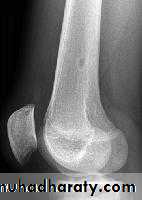

Rx : curettage + bone graftOsteoid osteoma

Patient < 30 yrPain > at night relieved by aspirin

In spine painful scoliosis

No malignant potential

XR : radioluscent nidus surrounded bysclerosis

Any bone except the skull

Rx : removal of nidusosteoblastoma